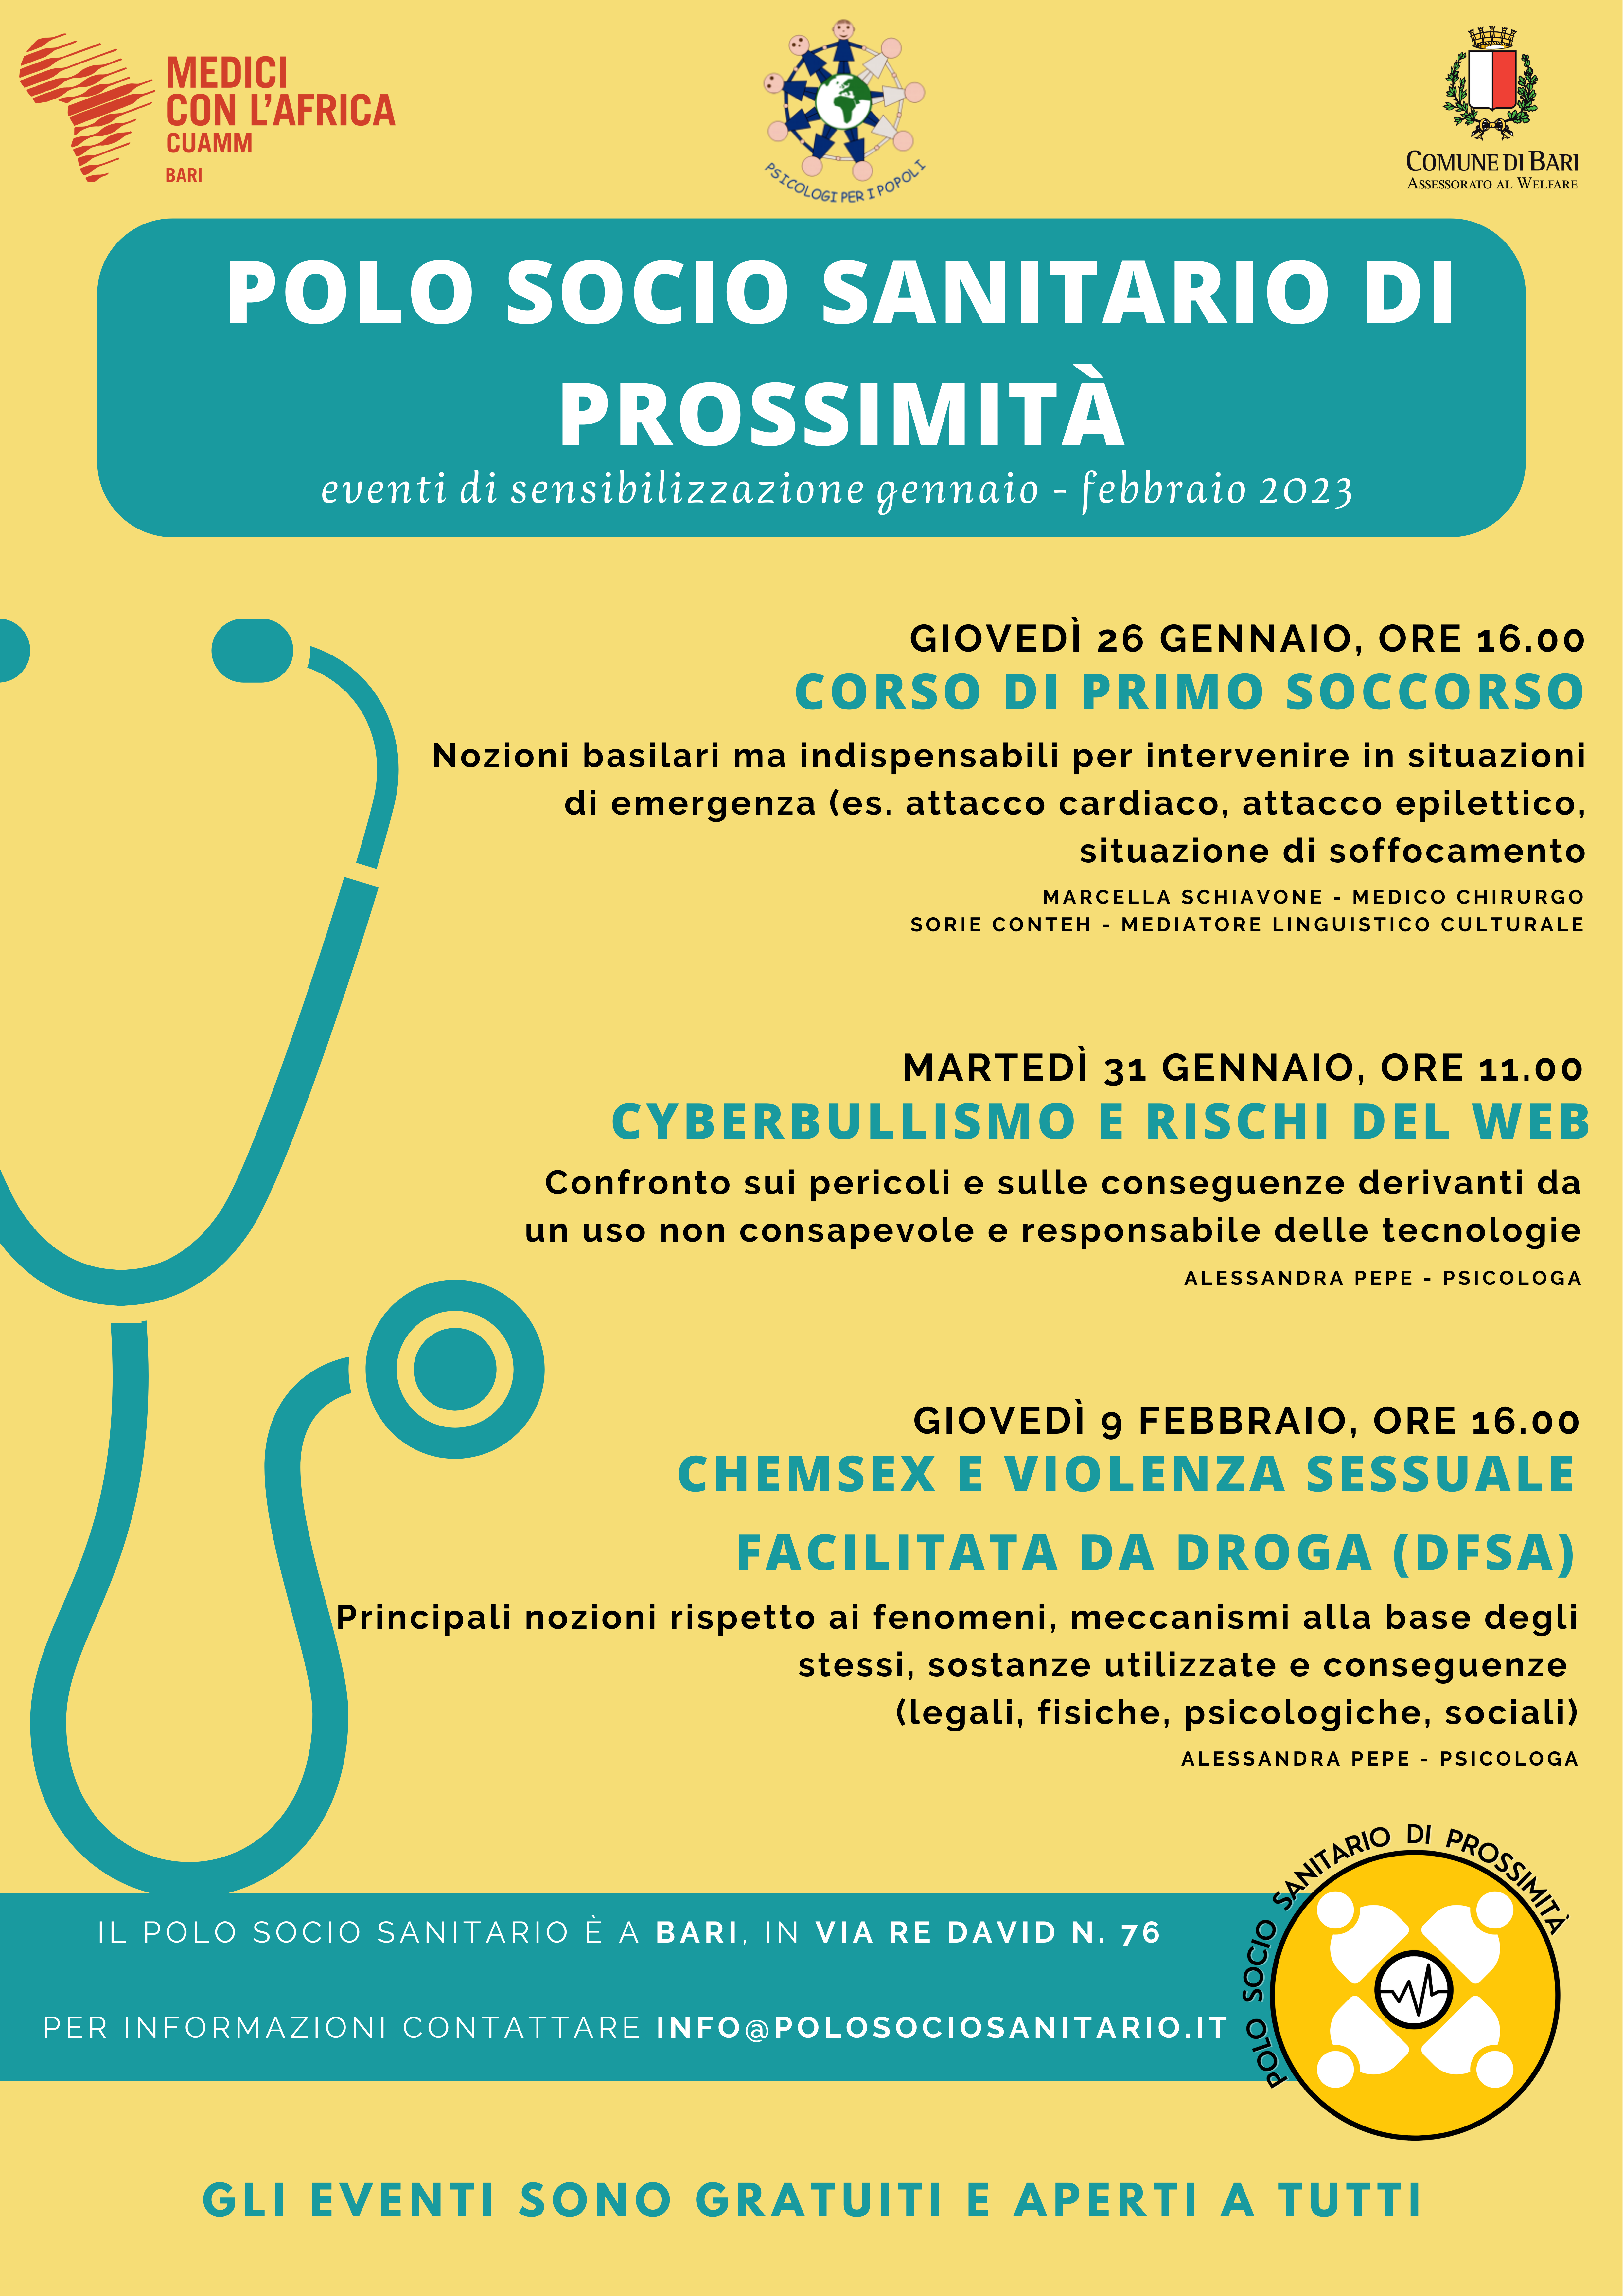

Bari

Evento dedicato alle produzioni musicali originali nel genere d'autore e popolare. Vai all'evento

Bari

Domani, martedì 21 settembre, alle ore 11.30, il sindaco Antonio Decaro interverrà alla cerimonia di intitolazione del giardino situato tra viale Kennedy e via Jan Palach, a Poggiofranco, alla memoria di Monica Dal Maso, educatrice, formatrice mediatrice culturale ed esperta in comunicazione interculturale ed economia[...] Vai all'evento

Bari

La festa, in programma nel giardino Giacomo Princigalli il 25 e 26 settembre, è il risultato di un processo di sviluppo interculturale del nostro territorio. L'idea di una grande festa condivisa nasce dalla convinzione che l'incontro tra realtà culturali differenti e la moltiplicazione degli sguardi siano una fonte[...] Vai all'evento

Bari

L’iniziativa, nata per ricordare Mimmo Bucci, front man del gruppo “La combriccola di Vasco”, travolto e ucciso da una moto pirata sul lungomare di Bari la notte del 15 maggio 2007, ha l’obiettivo di dare spazio e voce ai giovani musicisti, e allo stesso tempo di offrire loro un’occasione per emergere[...] Vai all'evento

Bari

Nell’ambito del festival Teatriamo 2021, sostenuto dall’assessorato alle Culture del Comune di Bari, il centro artistico-culturale Il Sipario organizza presso il Teatro Abeliano, venerdì 1 ottobre, alle ore 20, il talk di Dietro le quinte speciale libri. Il format, in onda su 50 emittenti in Italia, è condotto[...] Vai all'evento